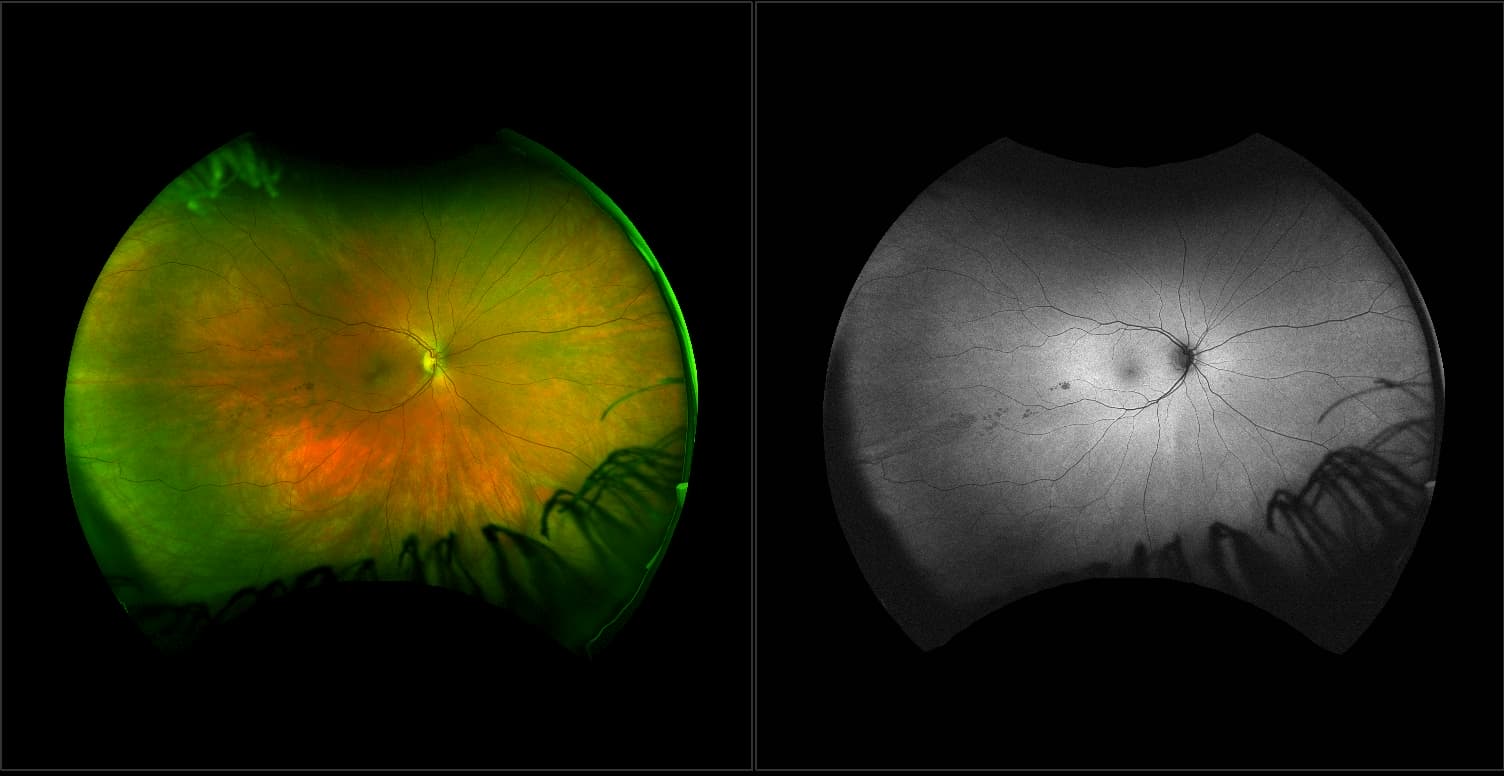

California - Large Pars Plana Cysts - Steered, RG

Pars plana cysts are a common peripheral retinal pathology that do not raise much clinical concern. They do not affect the central vision and observation alone is typically recommended. Pars plana cysts are something to be considered when peripheral retinal elevation is noted on routine exam.